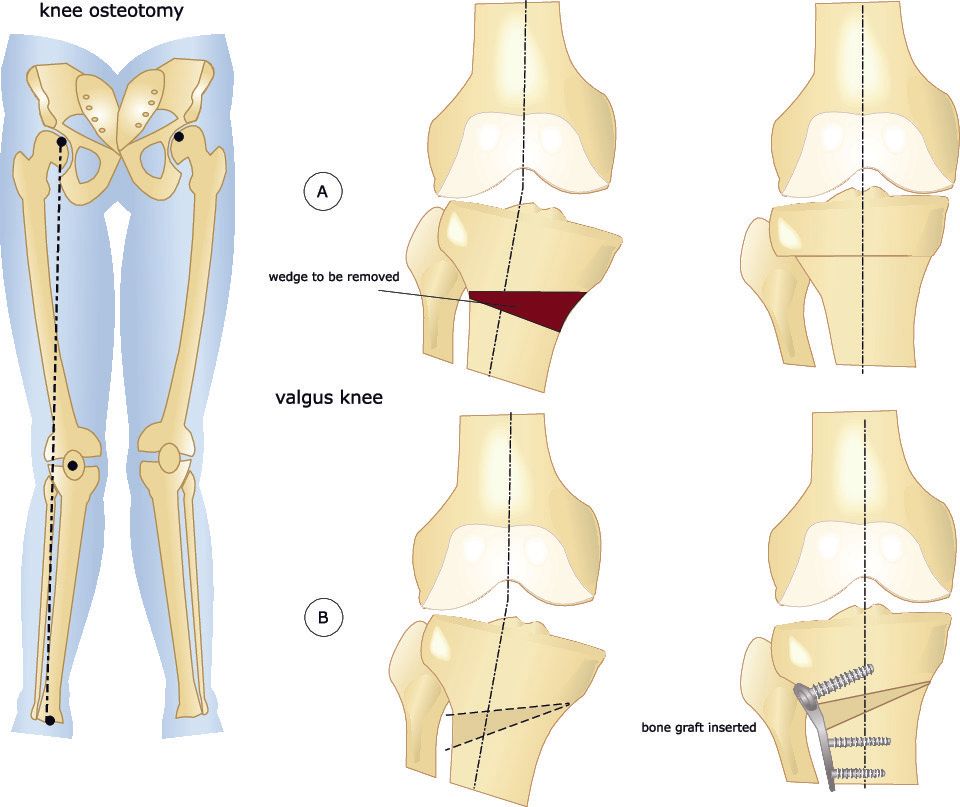

- Distal Femoral Osteotomy (DFO):

- This involves cutting the femur (thigh bone) close to the knee but not affecting the knee joint surface

- Realigning the femur and holding it in place with metalwork

- This is most commonly performed for valgus knees

- Both the high tibial and the distal femoral osteotomies can be performed:

- Opening wedge:

- This involves making a single cut in the bone and opening up the gap

- Closing wedge:

- This involves making two cuts to the bone that converge together in order to remove a wedge of bone

- The gap is then closed by bending the bone at the small

- A valgus knee deformity can be corrected with a medial closing wedge osteotomy (more common) or a lateral opening wedge osteotomy of the proximal (upper) tibia

- In an open wedge osteotomy a clamp is placed within the bone cut and the gap opened to the desired amount

- Depending on the size of the gap bone graft may be used to fill the gap

- In a closed wedge osteotomy two bone cuts are made to the bone (instead of one) so that a wedge of bone can be removed and then the bone realigned to close the gap and the bone ends to touch

- With both open and closing wedge osteotomies the osteotomy is secured with metalwork which is typically a plate and screws